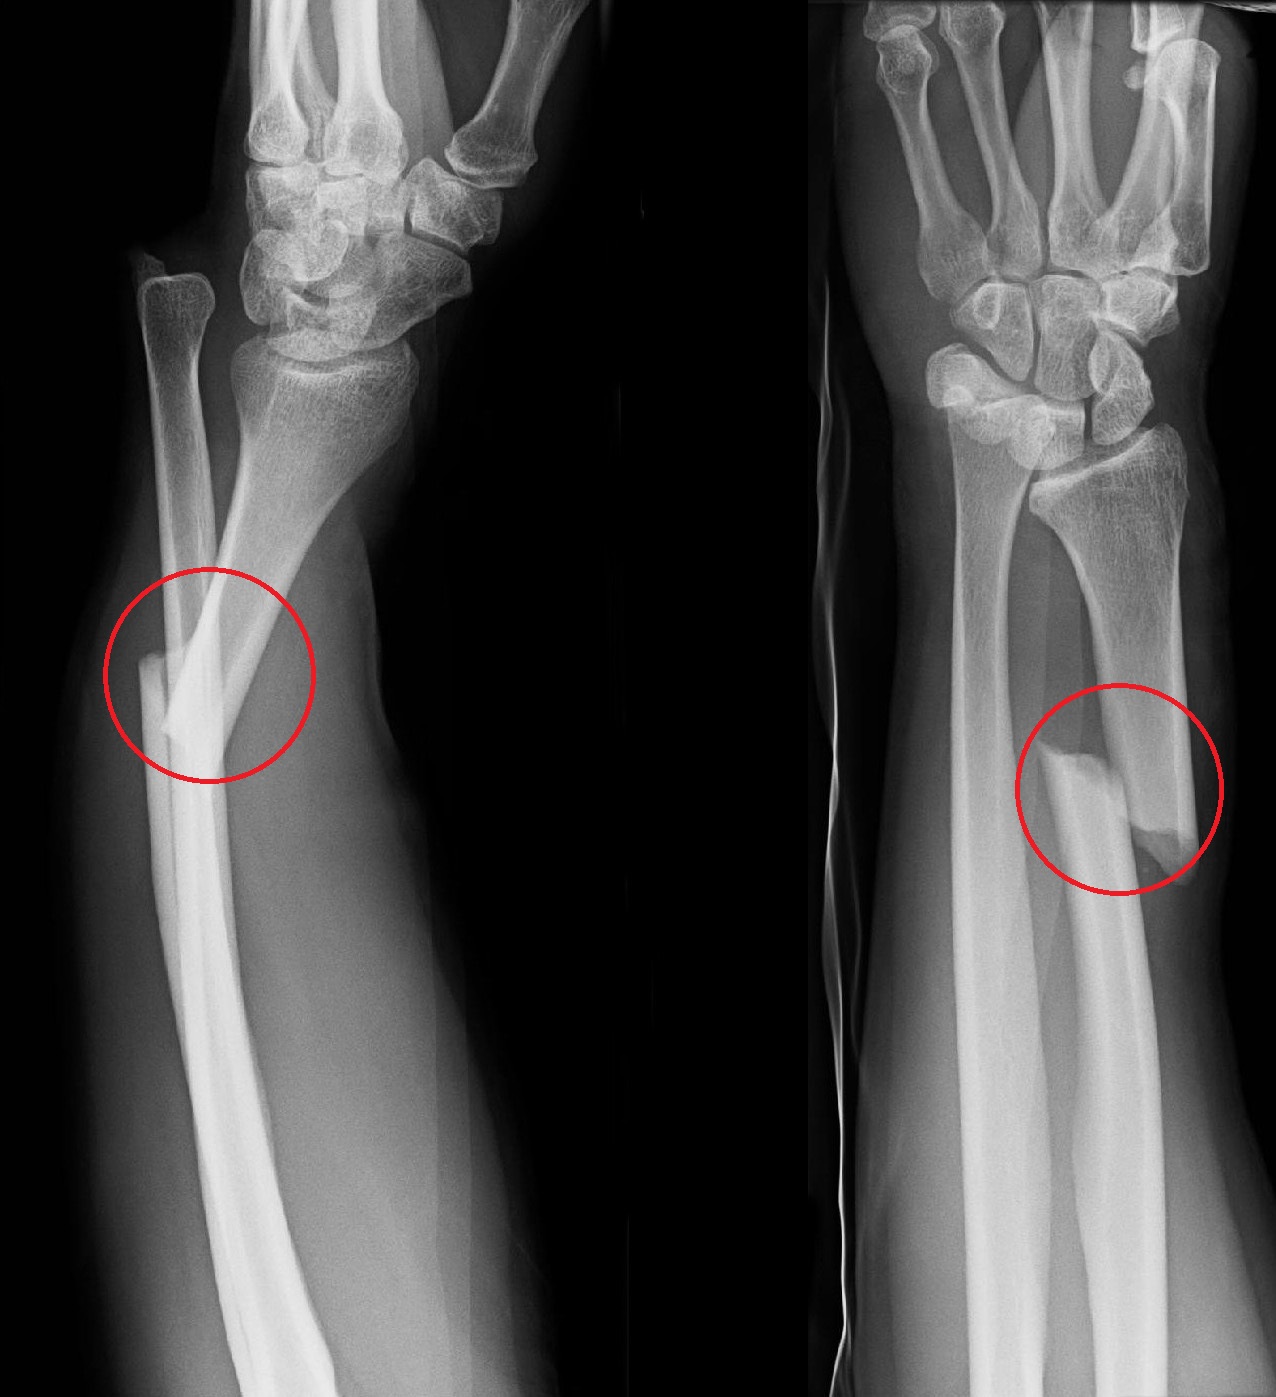

Anteroposterior and lateral radiographs demonstrating Galeazzi How To Reduce Galeazzi Fracture Galeazzi fractures are best treated with open reduction of the radius and the distal radioulnar joint (druj). • anatomic reduction of ulnar shaft fracture required for radial head reduction • assessment of radial head reduction after ulnar fixation • radiographic •. Galeazzi fractures are uncommon type of forearm fractures. Explain the treatment and management options available for. Clinical and radiographic. How To Reduce Galeazzi Fracture.

Galeazzi fracture Image How To Reduce Galeazzi Fracture A galeazzi fracture is a distal 1/3 radial shaft fracture with an associated distal radioulnar joint (druj) injury. Galeazzi fractures are uncommon type of forearm fractures. Explain the treatment and management options available for. Clinical and radiographic evaluation is consistent with a left distal radial shaft fracture with disruption of the distal radioulnar joint, known as a galeazzi. Galeazzi fracture. How To Reduce Galeazzi Fracture.

Galeazzi fracture Image How To Reduce Galeazzi Fracture Describe the typical imaging findings associated with a galeazzi fracture. Galeazzi fractures are best treated with open reduction of the radius and the distal radioulnar joint (druj). Clinical and radiographic evaluation is consistent with a left distal radial shaft fracture with disruption of the distal radioulnar joint, known as a galeazzi. A galeazzi fracture is a distal 1/3 radial shaft. How To Reduce Galeazzi Fracture.